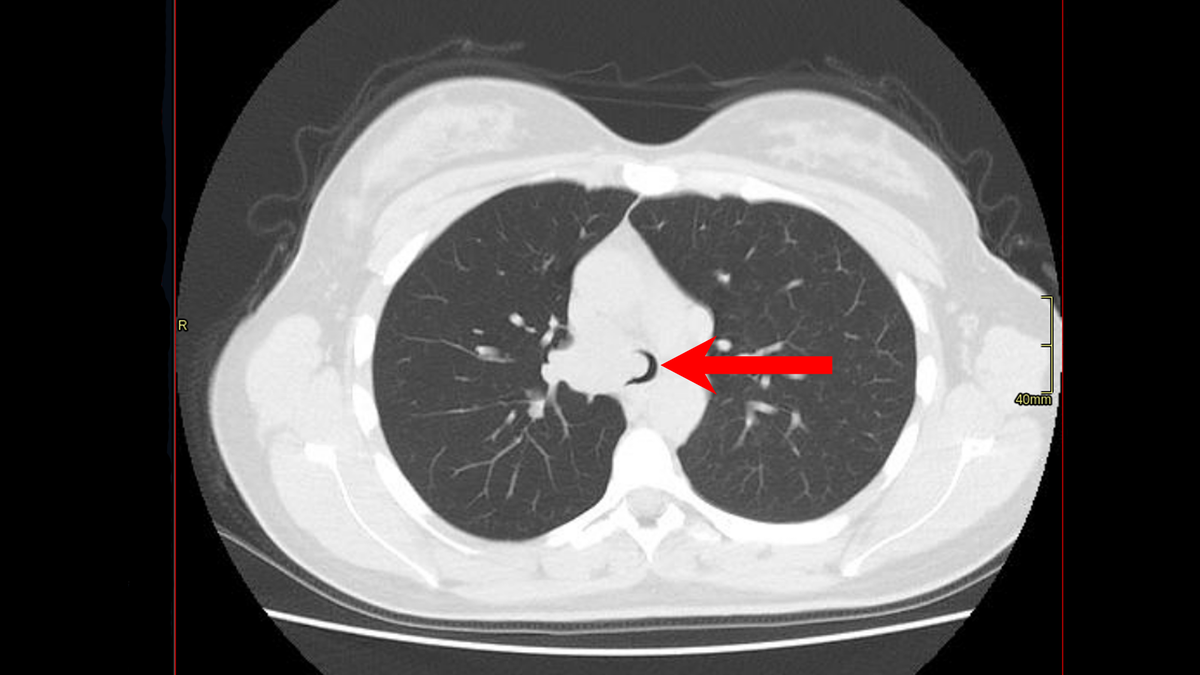

На компьютерной томографии, выполненной еще до всех вмешательств, мы видели опухолевую массу, которая практически полностью перекрывала трахею в нижней трети, а также главный бронх справа, верхнедолевой бронх.

...в составе ворот правого лёгкого определяется солидное объёмное образование с нечёткими, неровными контурами, неоднородно накапливающее контрастное вещество, максимальным измеряемым размером до 40х32мм, субтотально облитерирует просвет правого главного бронха, частичное сужение просвета трахеи на уровне бифуркации, распространение на стенку дистальных отделов трахеи...

На КТ указан верхнедолевой бронх справа, также полностью проходимый.